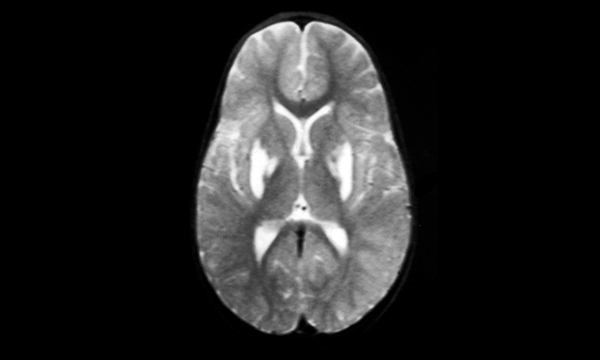

How to recognise and support children who have this rare neurological condition.